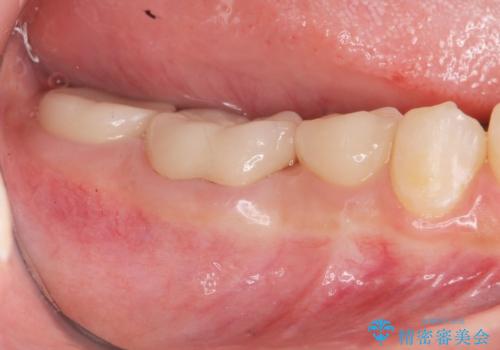

治療途中で長期間放置していたため、歯が歯ぐきから挺出(伸びてくる)してしまい、十分に強度を担保できるセラミッククラウンを装着するスペースが不足した状態です。

加えて、舌の邪魔になっている骨隆起や根尖病変といった問題を歯周外科・精密根管治療を行い、しっかりとスペースを確保したのちセラミッククラウンを作製していきます。